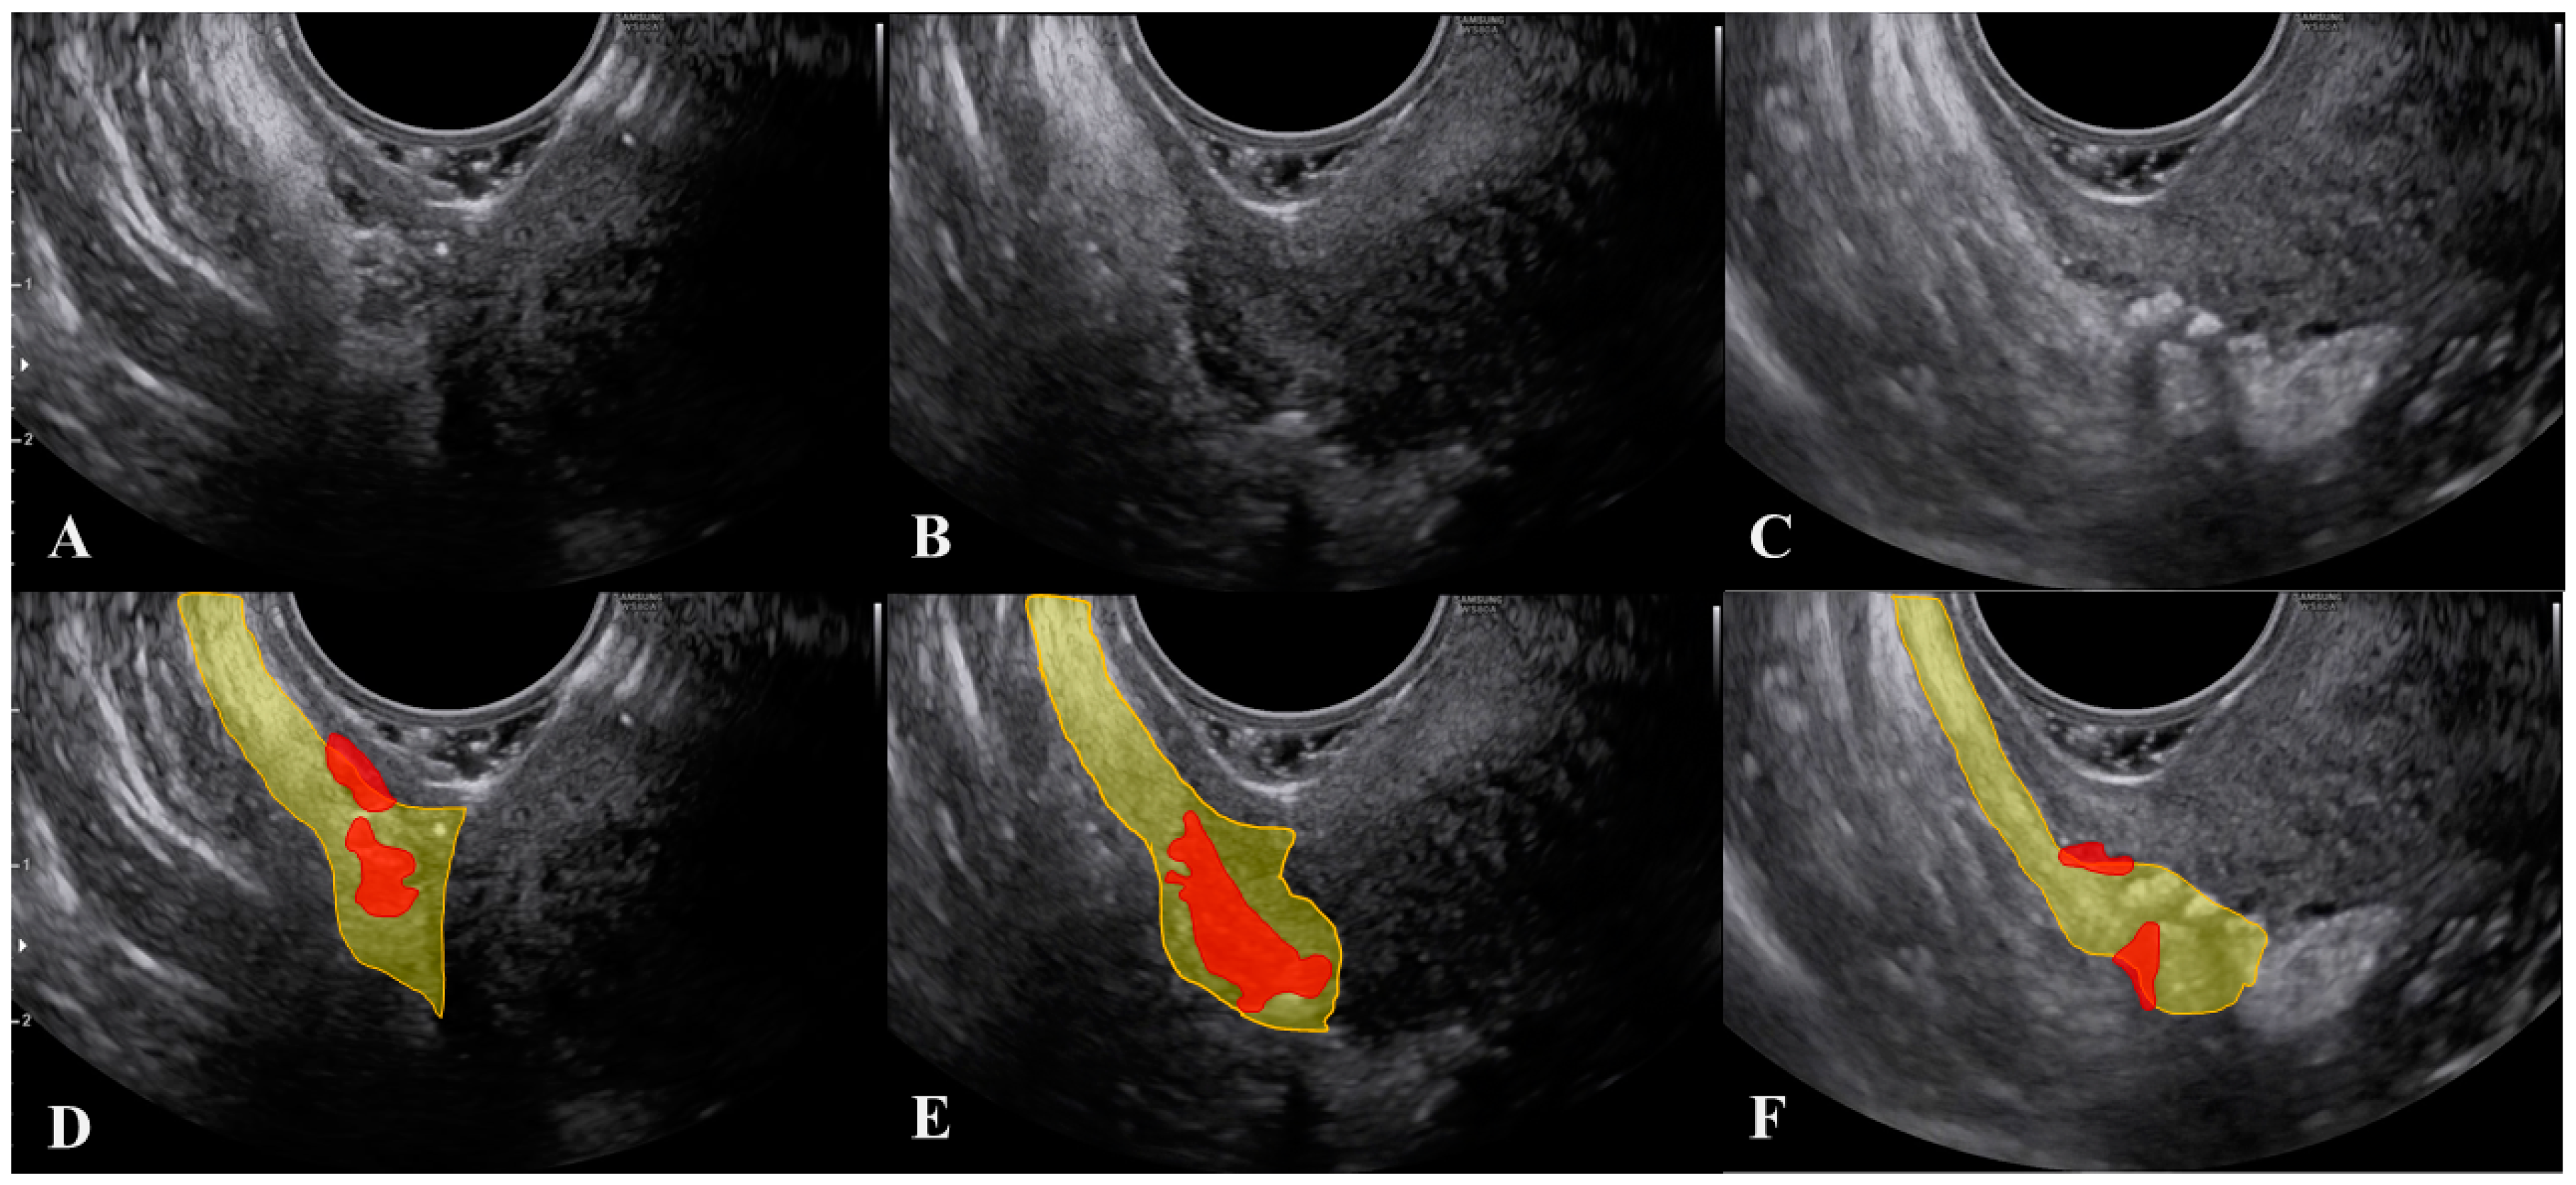

- Leonardi, M.; Martins, W.P.; Espada, M.; Arianayagam, M.; Condous, G. Proposed Technique to Visualize and Classify Uterosacral Ligament Deep Endometriosis with and without Infiltration into Parametrium or Torus Uterinus. Ultrasound Obstet. Gynecol. 2020, 55, 137–139. [Google Scholar] [CrossRef]